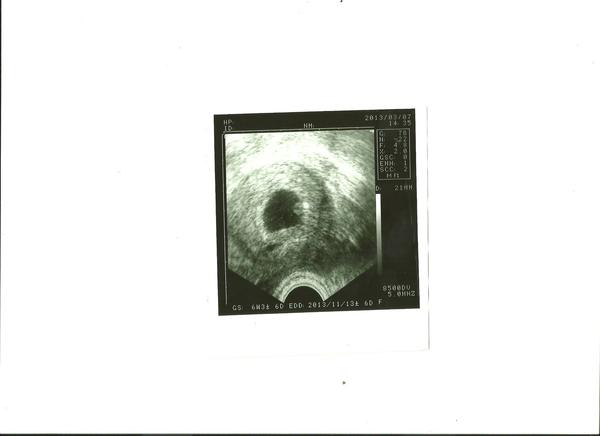

@zuza15 gratuluji k srdíčku. jsi v 2. měsíci a 7. týdnu v den kontroly. nevím, jak teď. jestli si chceš dát těhotenství do profilu, zapíšeš tam termín poslední menstruace a ono ti to bude počítat samo. nebo zkus www.tehotenskakalkulacka.cz.

jj už jsem to zkoušela ten odkaz co jsi mi poslala a ted mi to vychází dobře...Poslední mestrua,.jsem měla 21.1

@zuza15 Ahoj, tak tiše gratuluju a přeju, aby mimo pěkně rostlo. Na fotce vidím jen jedno, tak nevím, kde tam ta tvoje kamarádka viděla to druhé.

@matysikovad jasně díky....víš,jěště není tak všemu konec.....bojím se hodně a ted nejvíce ultrazvuků,protože jsem si toho dost se vším prošla....bych ti mohla tu fotečku poslat ,aby ses mrkla,??Neboj,taky se zadaří...vím,co to je,jak to bolí....a to čekaní,kdy se to zadaří atd....vím to a cítím s tebou.... 😉